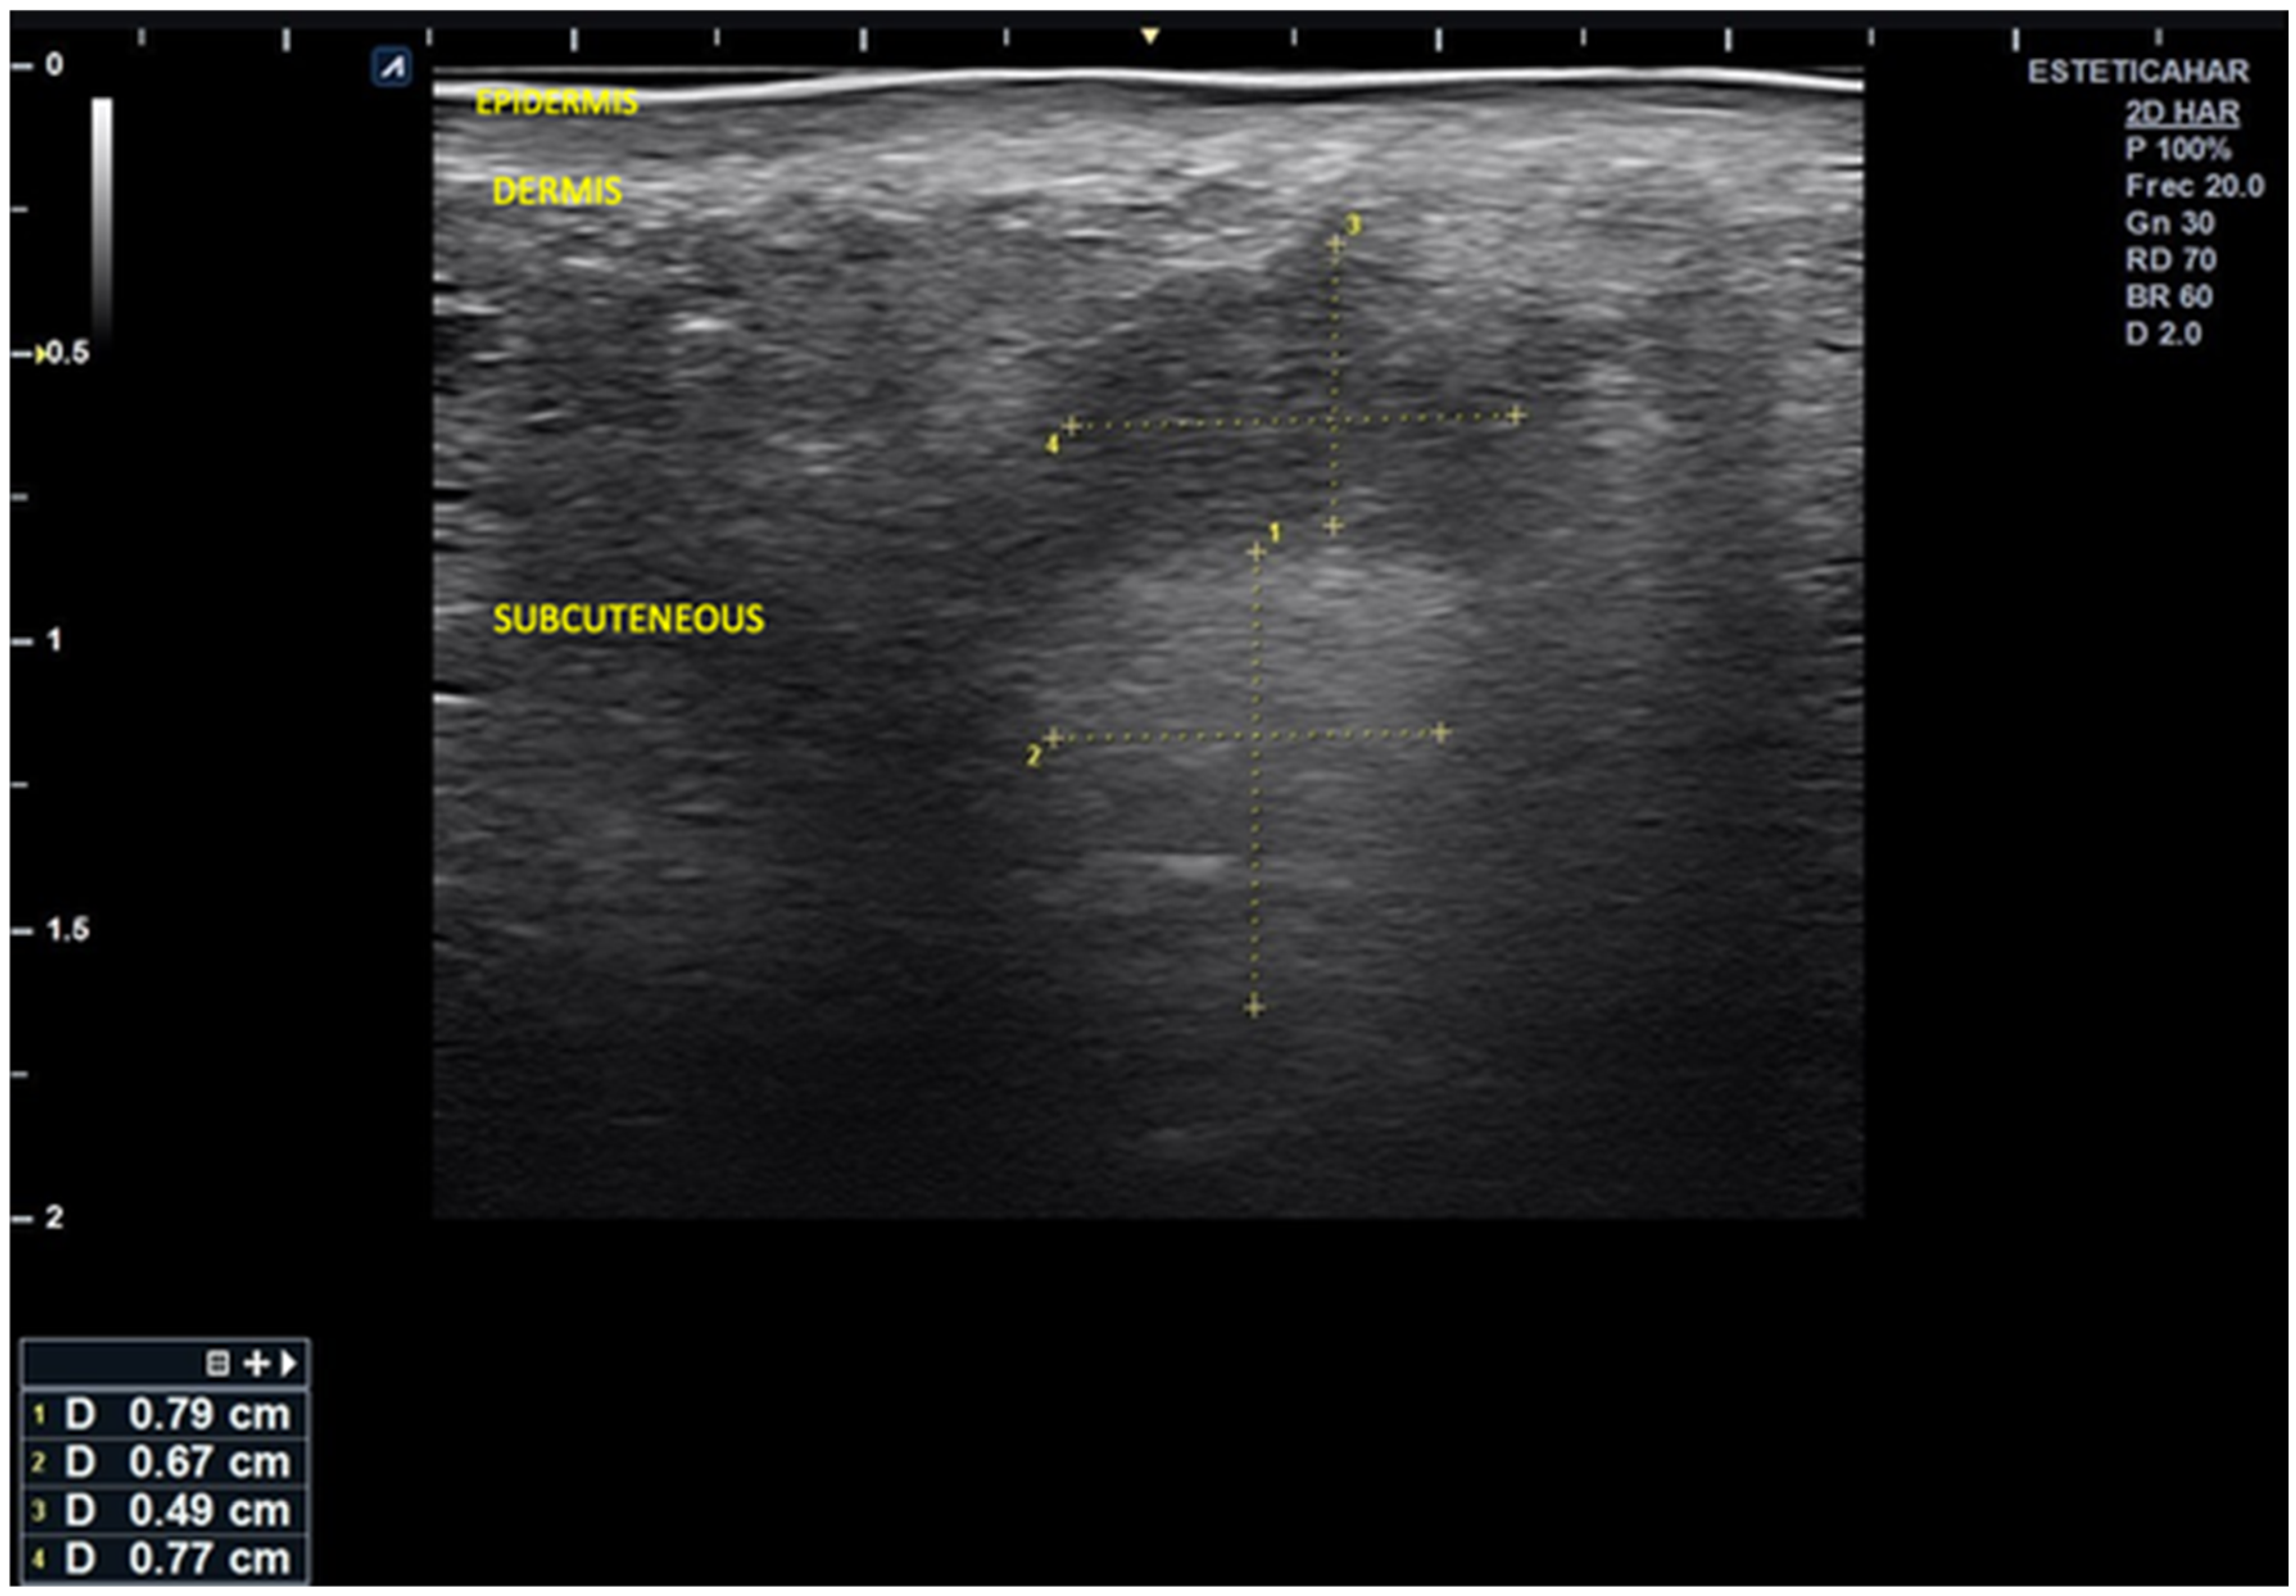

). The scan reveals alternating hyper- and hypoechoic columnar areas extending from the posterior dermis to the bone plane, which hinder clear differentiation of tissue layers based on echogenicity. The largest area, measuring 0.24 cm in width, is most likely associated with deposits of hybrid material (hyperdiluted collagen stimulator). Additionally, three smaller, rounded hypoechoic deposits are observed in the more superficial subcutaneous region. The largest of these measures 0.27 × 0.26 cm and is likely associated with poor integration of the injected material, without evidence of increased microvascularization.